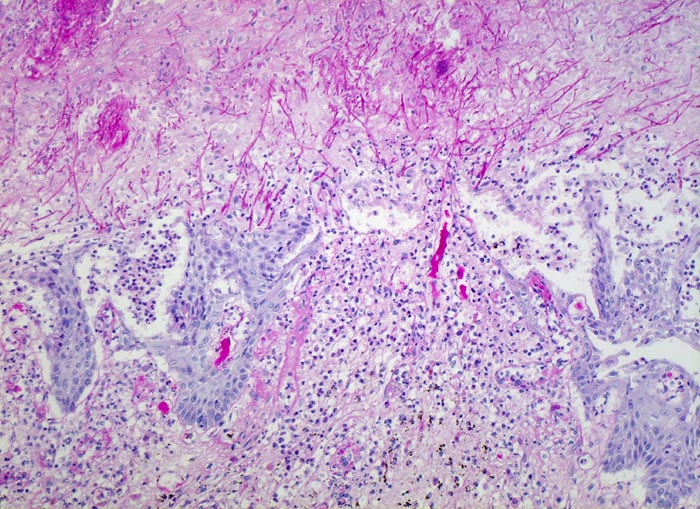

Endoskopisch finden sich abstreifbare weissgelbe krümelige Plaques, welche keine Prädilektionsstelle zeigen. Die Schleimhaut kann erodiert oder ulzeriert sein. In Klumpen von nekrotischen Plattenepithelzellen lassen sich mikroskopisch oft Sporen und Pseudohyphen nachweisen. Die Pseudohyphen wachsen oft senkrecht zur Epitheloberfläche. Besonders gut sichtbar werden die Pilze in der PAS oder Grocott Färbung. Zusätzlich besteht eine aktive Ösophagitis mit Infiltration der oberflächlichen Plattenepithelschicht durch neutrophile Granulozyten. Zahlreiche neutrophile Granulozyten in einem Ulkus weisen auf eine Soorösophagitis. Bei viral bedingten Ulzera (Herpes, CMV) prädominieren Makrophagen.

• Teils ulzerierte, teils erodierte Ösophagusmukosa.

• Die Pseudomembran über der ulzerierten Schleimhaut setzt sich zusammen aus einem dichten Netzwerk PAS positiver Soorpseudohyphen und ovale aussprossende Sporen, nekrotischem Plattenepithel, Fibrin und neutrophilen Granulozyten.

• Die Pseudohyphen infiltrieren das Plattenepithel.

• Im Unterschied zur Aspergillose dünnere Pseudohyphen ohne echte Verzweigungen und zahlreiche Sporen.